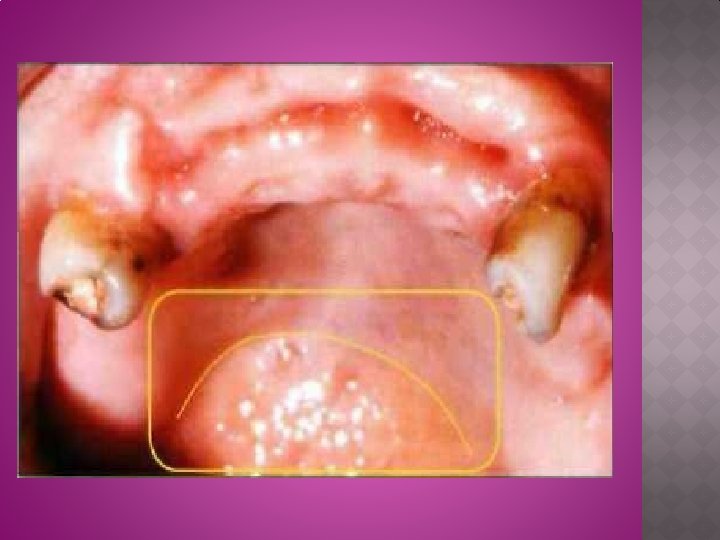

2)La papille rétro incisive : C'est un relief muqueux qui surplombe le trou palatin antérieur. Ce trou voit le passage d'un paquet vasculo-nerveux qu'il ne faut pas comprimer car cela peut aboutir à une ischémie. � ces zones sont soit à éviter , soit à décharger. 3)Zones de Schroeder : Ce sont des zones de tissus adipeux, non pathologiques, qui se diagnostiquent à la palpation. Elles se trouvent sur le palais dur en regard des première et deuxième molaires. De part et d’autre de la suture intermaxillaire. � Ces régions ont un comportement « élastique » . Qu’est un facteur négatif � de la technique d'empreinte, elles peuvent se déformer et par la suite, provoquer la désinsertion de la prothèse. La présence de ces particularités anatomiques indique des techniques d'empreinte non compressives